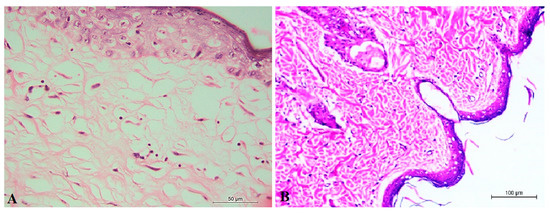

3.4.4. Histopathological Examination of Optimum ALN Gel Formulation